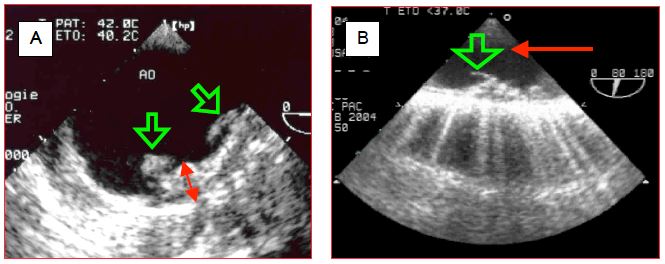

Figure 7.36 : Deux images ETO d'athéromatose de l'aorte descendante. A: Les masses athéromateuses sont protubérantes dans la lumière et la surface endovasculaire complètement irrégulière; la double flèche rouge en indique l’épaisseur (environ 1 cm). B: Un athérome pédiculé flotte dans la lumière comme un grelot; cette situation est hautement emboligène. La flèche rouge indique le sens du flux.

L'examen de l'aorte descendante permet de décider si l'athéromatose est telle qu'elle contre-indique le placement d'une contre-pulsion intra-aortique (CPIA) avant la sortie de CEC (Figure 7.36) (Vidéo).